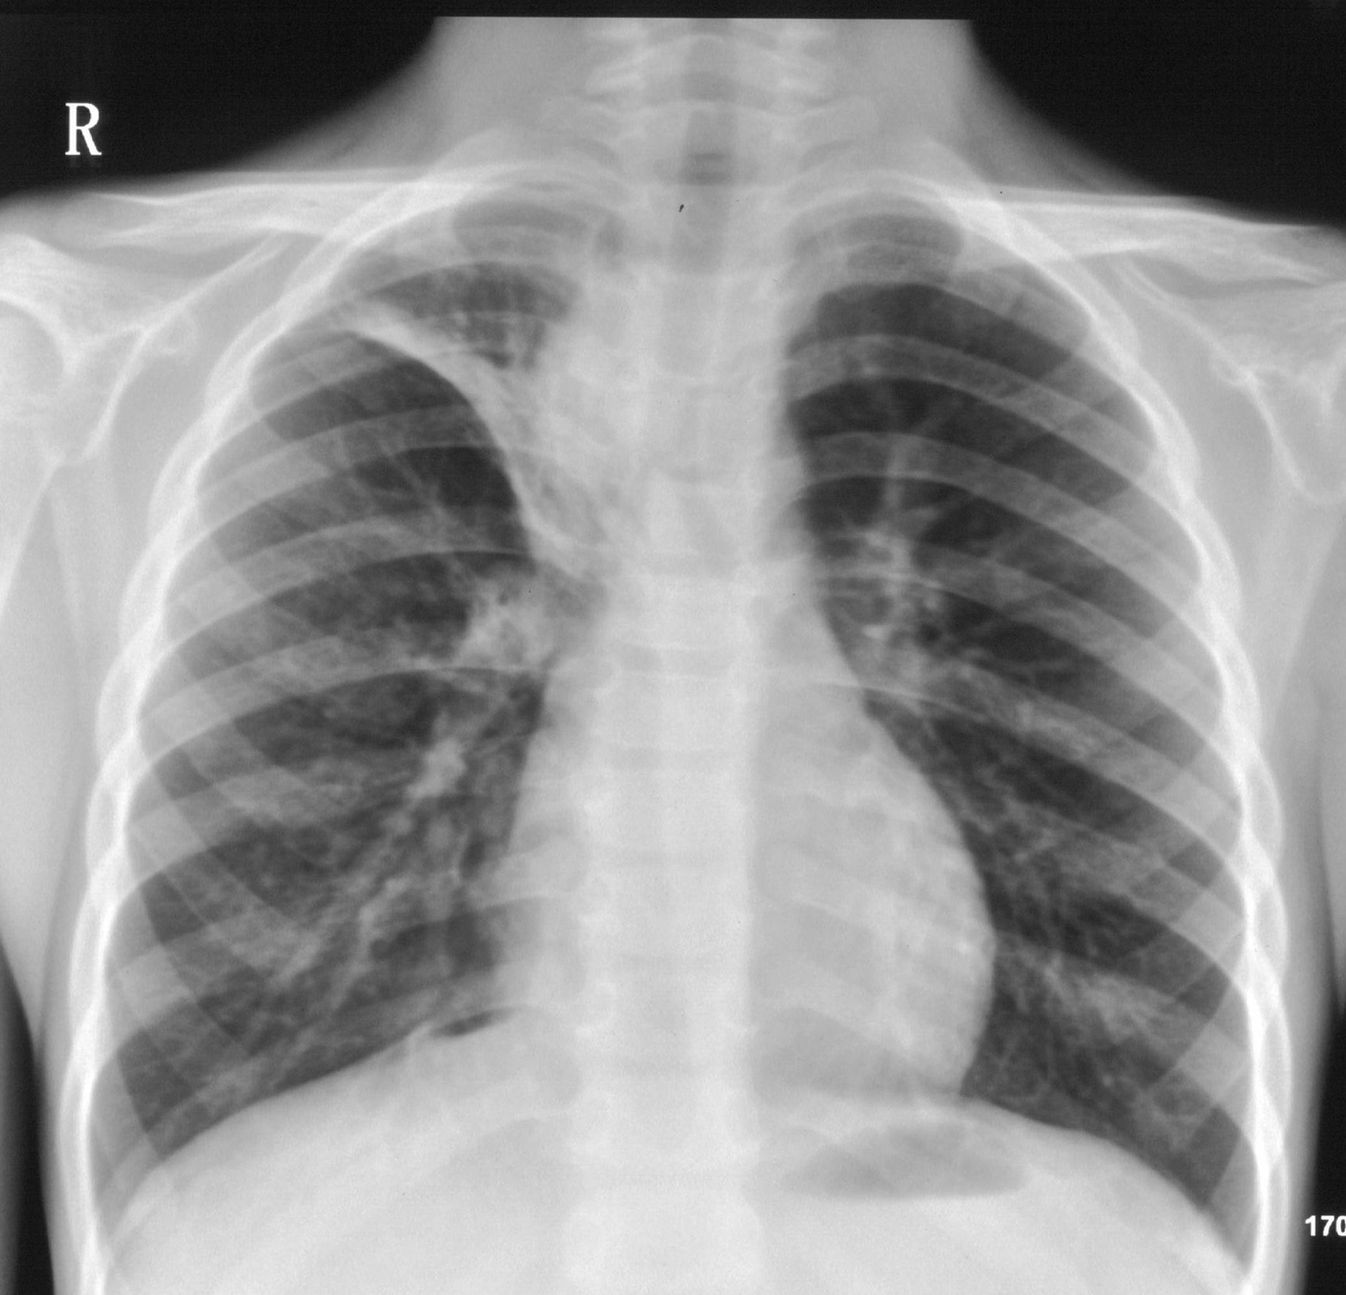

9月20号平片检查情况:

右上肺不均匀密度增高,体积变小,水平裂弧状上移,纵隔内有肿大的淋巴结。考虑:

1、右上肺炎(吸收期),纵隔淋巴结肿大压迫右上叶肺膨张不全

2、纵隔淋巴结结核不能排除

建议继续抗炎治疗短期复查